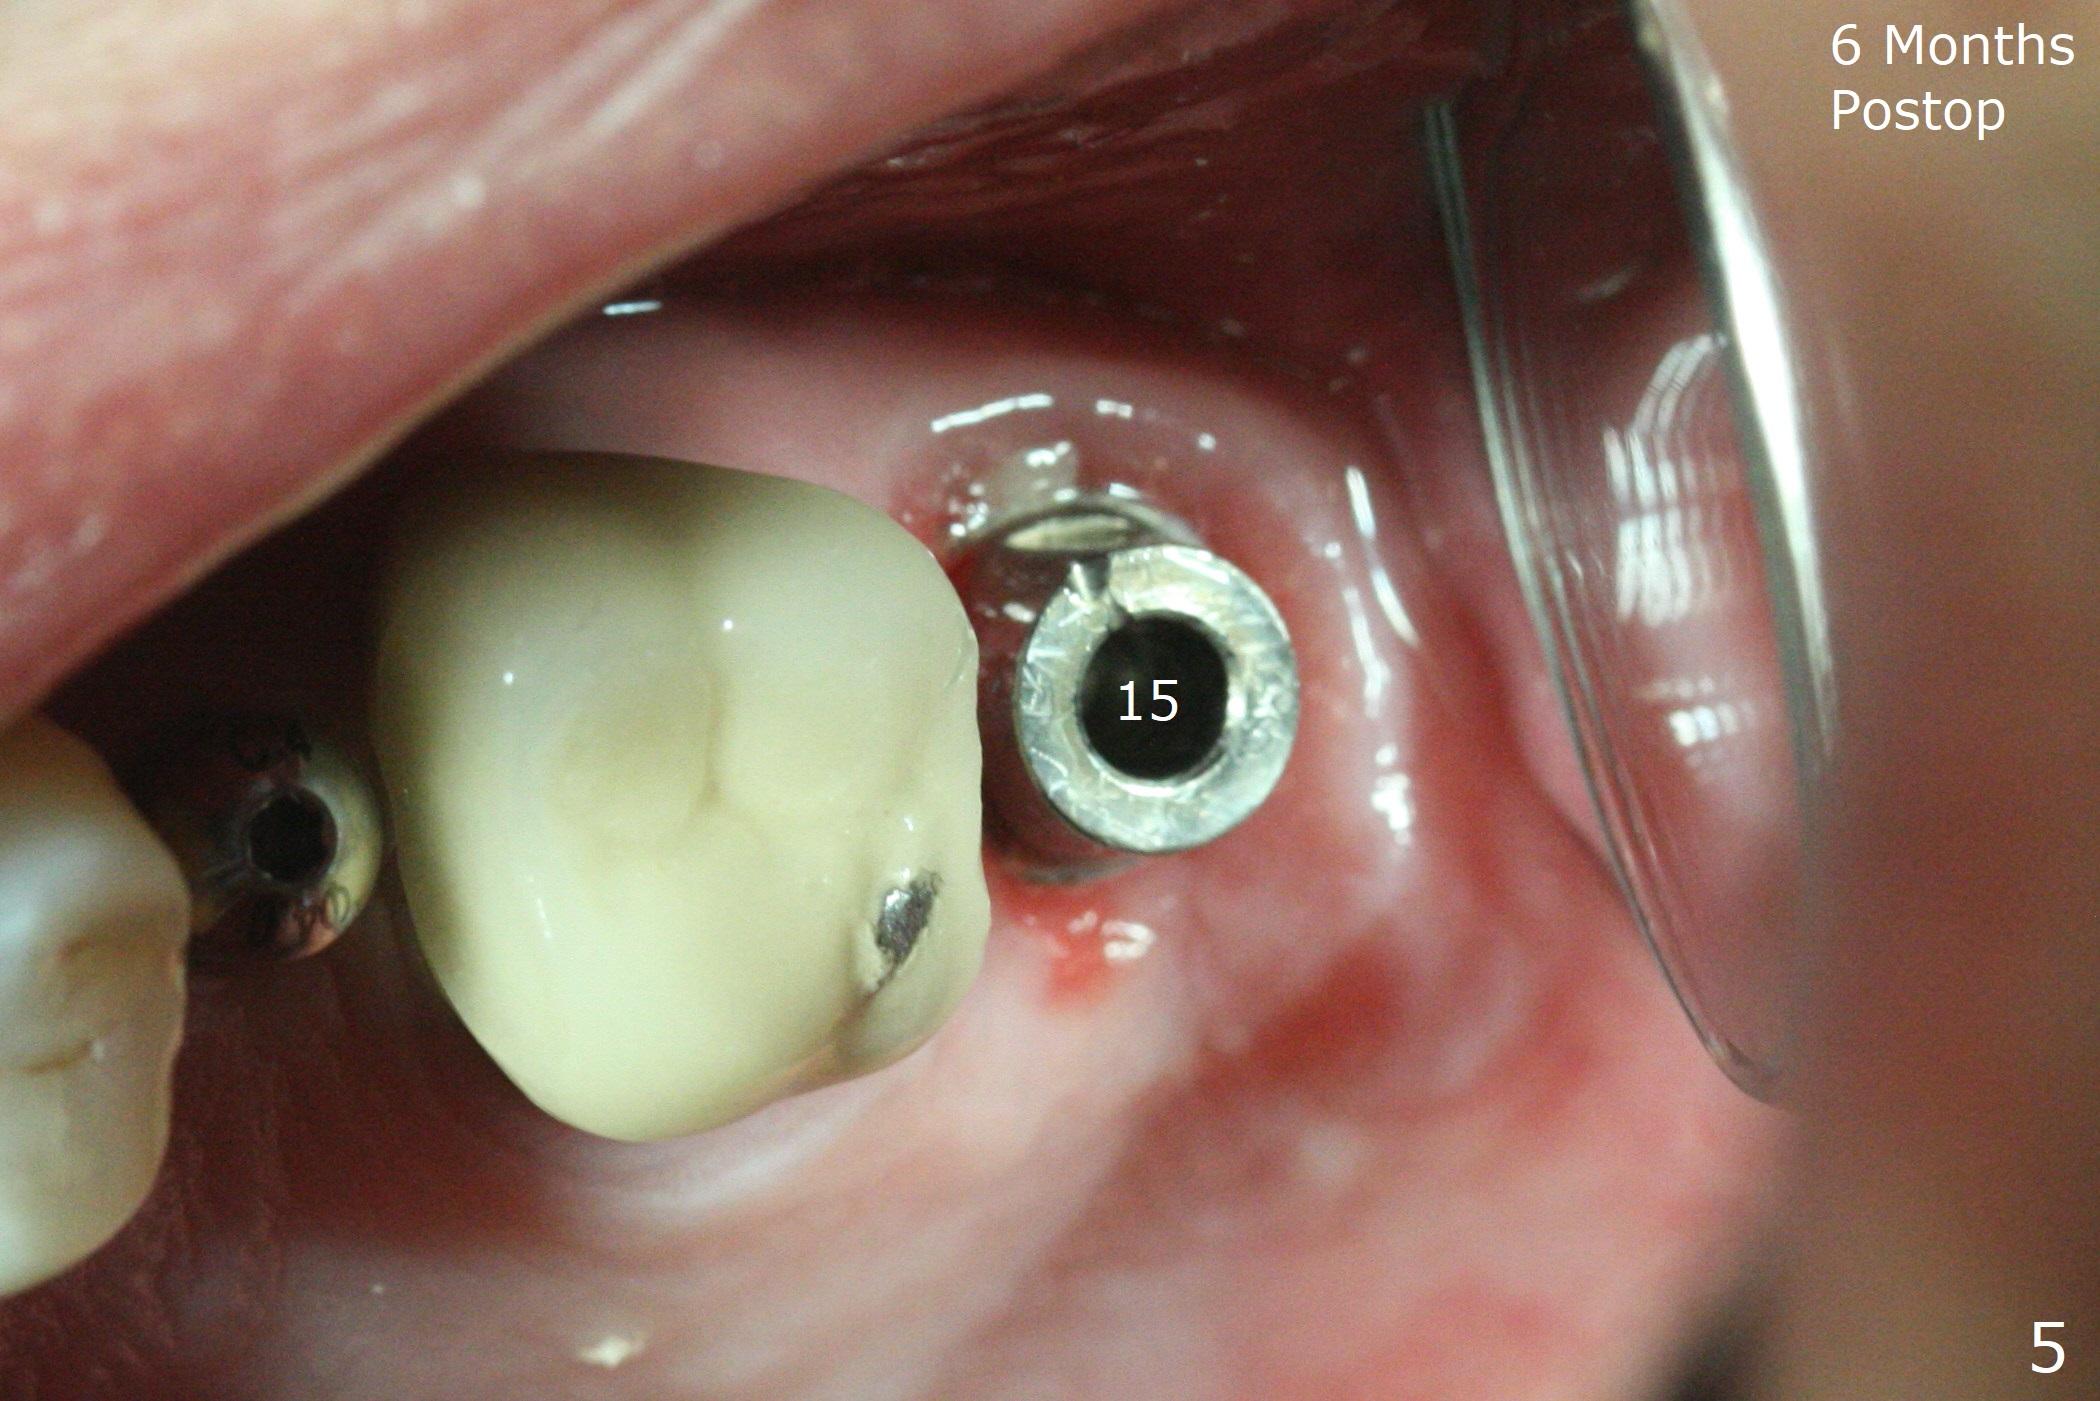

The palatal gingival margin of the tooth #15 with vertical root fracture is low, consistent with the low palatal plate after extraction (Fig.1 >). With IS guide, a 5x11 mm IBS implant is placed in the septum with >5 mm the palatal gap. After underprep in depth, a 3.5x9 mm achieves primary stability (Fig.2,3). The palatal defect is repaired with allograft (*) and 2 pieces of PRF membrane. The palatal soft tissue defect appears to have been repaired 6 months postop (Fig.4,5). When a narrower abutment with longer cuff is placed at #15 (6x4(4) mm in Fig.6, as compared to 6.5x4(3) mm one in Fig.2), there is no gap between the implant and abutment. In contrast there is one at #13 (Fig.6 <) when a 4x4(4) mm abutment is seated following removal of a 4x4 mm healing abutment. After use of a 4.6 mm profile drill, the gap disappears (Fig.7). Impression is taken.